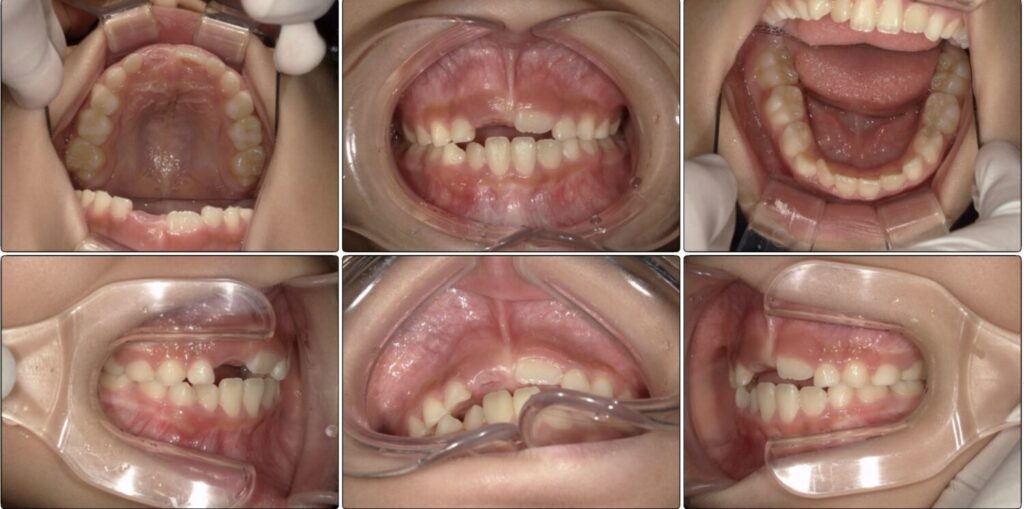

治療前 / 現在

治療開始時

現在

初めに撮った時の写真です。

上の歯と下の歯は噛んでいますが、歯と歯が先端でピッタリ噛んでいます。

先ほどの写真と比べてもらうと上下の歯が当たりすぎています。

最初の頃は上下の歯と歯がぴったりで噛んでいましたが、上の顎の写真の時と同じ日の噛み合わせ写真です。

まだ生えてる途中ですが以前より上下の差があります。